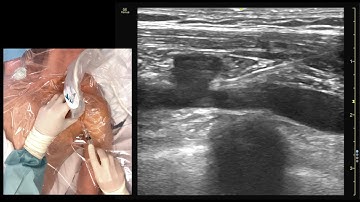

Central Line Academy: In-plane Long-axis